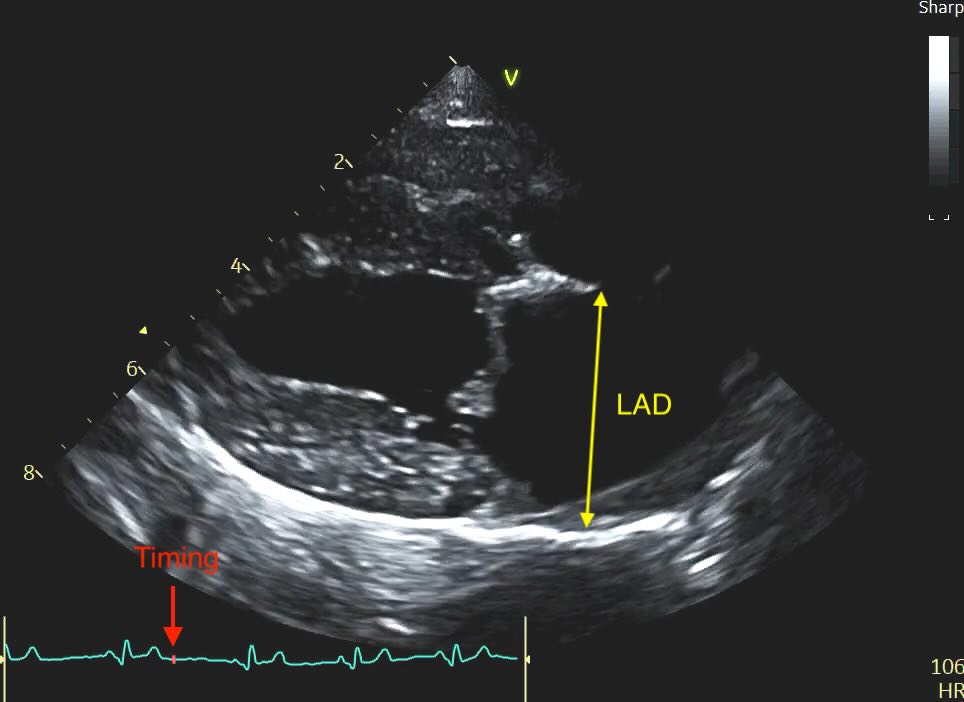

Methodology and Timing

Unlike the LA:Ao, which we time to early diastole, the LAD is measured at end-systole. This is when the left atrium is at its maximal volume, having just finished filling from the pulmonary veins.

- The Timing: Select the frame just before the mitral valve opens (or 1-2 frames after the peak of the T-wave if using an ECG). This is easy with practice, scroll backwards in your loop until you have a closed valve, then step forward frame by frame until it pops open, and go back again 1 frame.